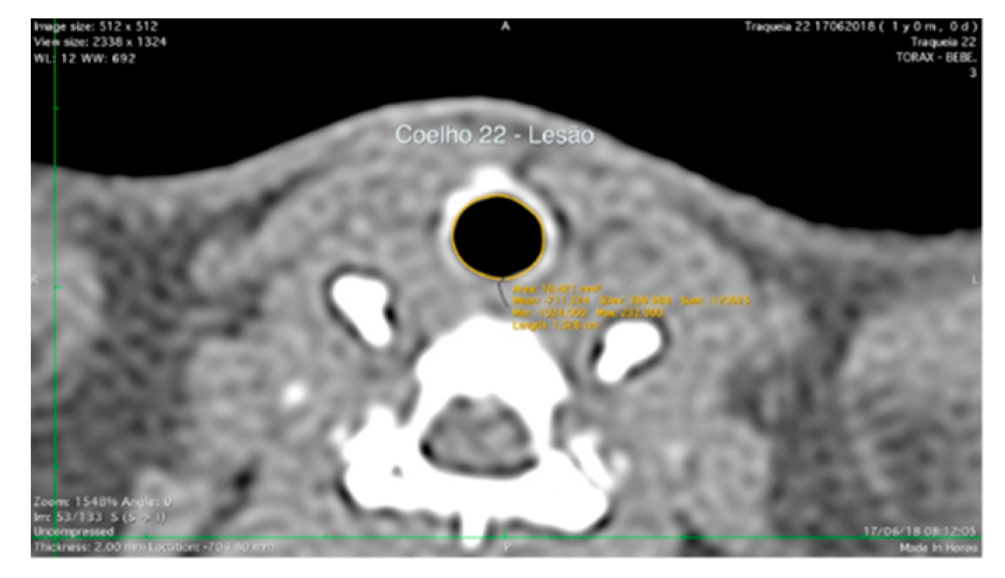

2.6. Computed Tomography Scanning Analysis

The scanned computed tomography images of each animal were taken at settings of 90 kV, 60 µA, and 280 ms, with a resolution of 512 × 512 in Digital Imaging and Communication in Medicine (DICOM) reader (OsiriX, version 6.5; Pixmeo, Bernex, Switzerland) in transverse and sagittal reformats (Figure 3). The lesion area was calculated from 2D reconstructed images using Horos Version 3.3 software (Geneva, Switzerland).

Figure 3.

Post-contrast transverse computed tomographic images of the tracheal in a rabbit.

The analysis with specialized image software provided quantitative data of the average transversal area of the lumen. After 60 days, the computed tomography analysis revealed that the average tracheal lumen area of the lesion region in the AM + hucMSCs group was increased compared with the AM group and the C group, although there was no significant result, with p = 0.211. Comparing the areas without injury to the groups, we did not observe any significance between them, demonstrating homogeneity between the groups, with p = 0.811 (Table 1).